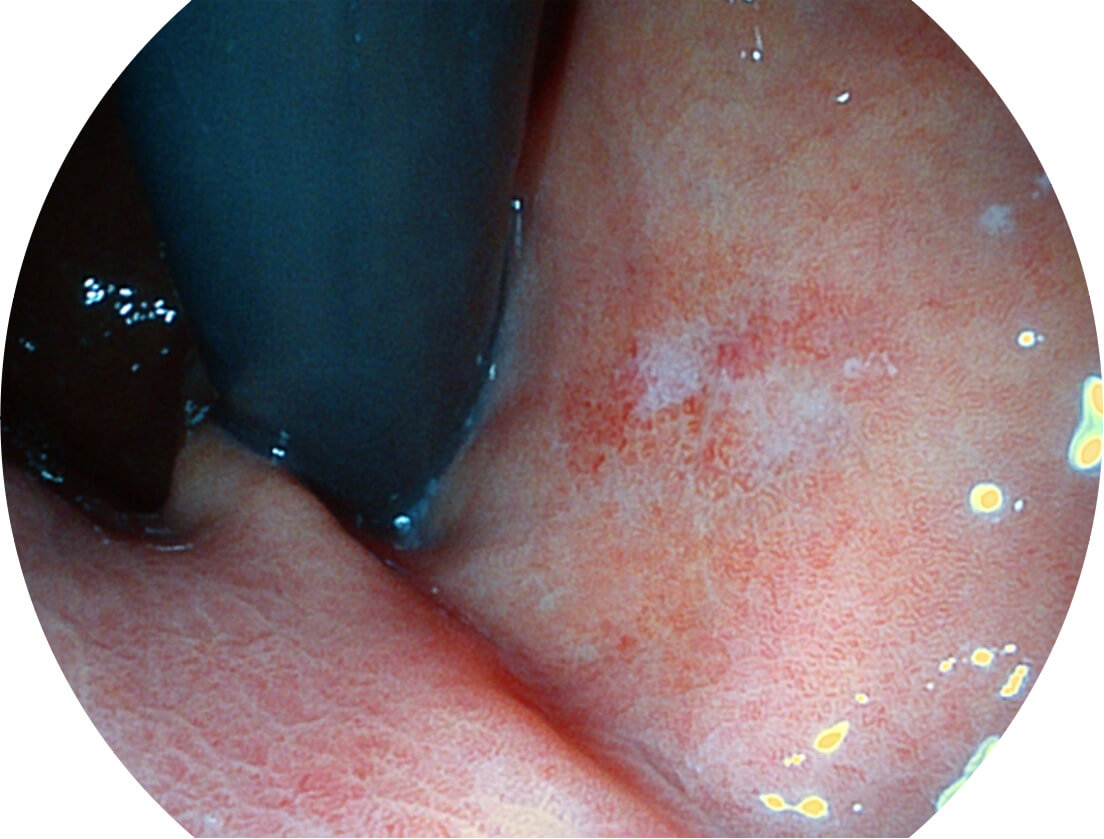

Spectral Focused lmaging, SFI

图像具有高亮度、高黏膜血管颜色对比度的特点,且不改变粘液、食物残渣、粪便的基本颜色,可在中远景下进行观察,助力消化道早期疾病的诊断。

SFI图像